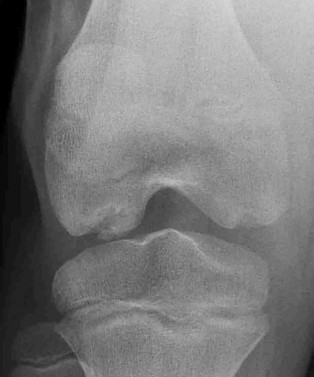

A 3-year-old female presents with progressive unilateral genu varum. Standing lower extremity radiographs are obtained. Measurement of the metaphyseal-diaphyseal angle (Drennan's angle) is most predictive of progression to infantile Blount's disease when it exceeds what threshold?

Explanation